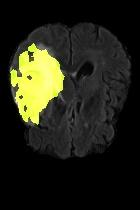

Current unsupervised anomaly localization approaches rely on generative models to learn the distribution of normal images, which is later used to identify potential anomalous regions derived from errors on the reconstructed images. However, a main limitation of nearly all prior literature is the need of employing anomalous images to set a class-specific threshold to locate the anomalies. This limits their usability in realistic scenarios, where only normal data is typically accessible. Despite this major drawback, only a handful of works have addressed this limitation, by integrating supervision on attention maps during training. In this work, we propose a novel formulation that does not require accessing images with abnormalities to define the threshold. Furthermore, and in contrast to very recent work, the proposed constraint is formulated in a more principled manner, leveraging well-known knowledge in constrained optimization. In particular, the equality constraint on the attention maps in prior work is replaced by an inequality constraint, which allows more flexibility. In addition, to address the limitations of penalty-based functions we employ an extension of the popular log-barrier methods to handle the constraint. Comprehensive experiments on the popular BRATS'19 dataset demonstrate that the proposed approach substantially outperforms relevant literature, establishing new state-of-the-art results for unsupervised lesion segmentation.